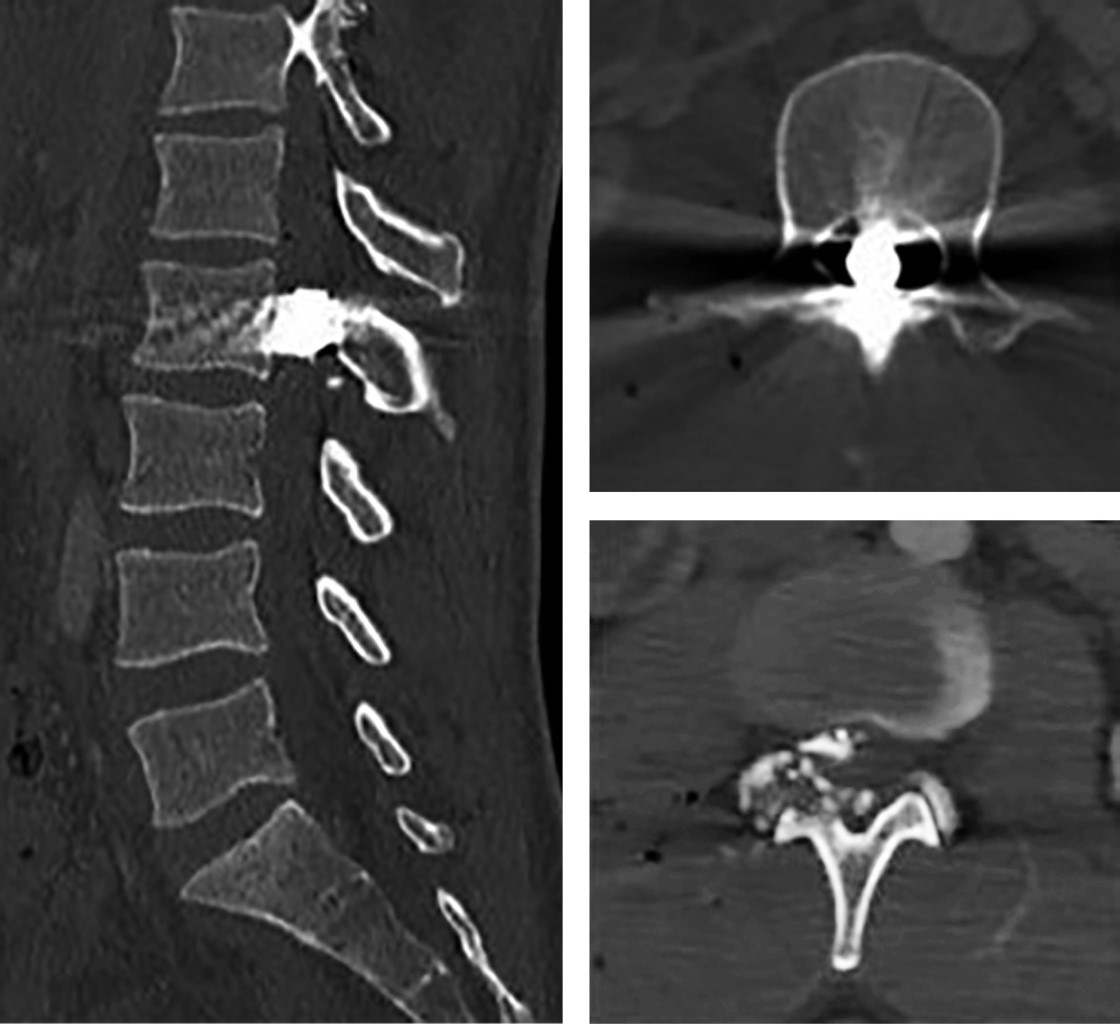

Morphological classification of wounds caused by a fire weapon in spinal column

Gunshot wounds to the spine have shown an increase worldwide due to the increase in possession of firearms in the civilian population as well as the increase in drug trafficking and consumption in all countries of the world. According to the most recent epidemiology available in current literature, an increase in this type of firearm injuries has been observed during and after the SARS-CoV-2 contingency in 2019, in the main cities of the United States of America such as Nueva York, Chicago and Los Angeles. The treatment of this type of injury continues to be controversial in certain aspects, and without a unified consensus as referred to in the world literature, starting from the parameter that surgical treatment of the spine is indicated when there is a neurological damage with evidence of compression at the level of the spinal cord and site of injury, due to spinal instability and proximity of the projectile to the neurological canal or spinal canal. It must be taken into account that the anatomy of each vertebra according to the segment increases the possibility of associated injuries, such as in the thoracolumbar spine due to its proximity to the abdominal organs, and in turn favors the risk of contamination of the wound, making it essential to modify the treatment scheme. antibiotic according to the segment of the spine affected. The objective of this work is to propose a classification for gunshot wounds to the spine "TLEP" that is reproducible and can facilitate an evaluation algorithm in the future, to develop a prognostic scale for the unified treatment of these injuries.

Figure 1

Figure 2

Figure 3